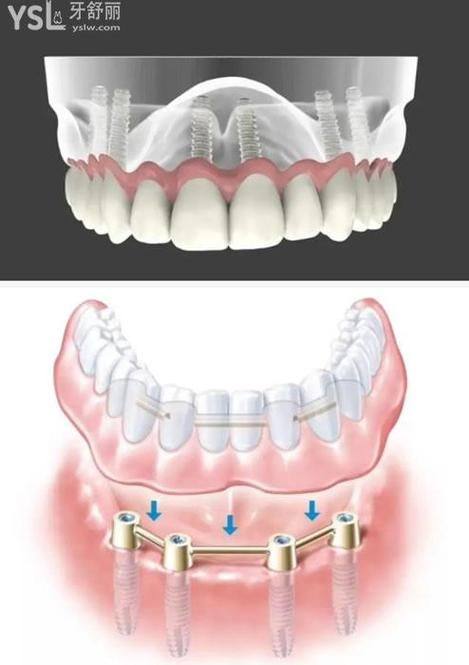

全口/半口种植牙及即刻种植修复:可开展全口即刻种植、即刻负重种植牙手术,针对老年全口无牙颌患者有着丰富的诊疗经验,能够通过精细的种植方案修复患者正常咀嚼功能。

口腔修复与义齿修复:可开展全冠牙、烤瓷牙、固定义齿、活动义齿以及全口无牙颌BPS修复等项目,满足不同患者的义齿修复需求。

常规口腔诊疗项目:涵盖韩国奥齿泰Osstem种植、即刻种植牙、洗牙、球面自锁托槽矫正、根管治疗等项目。